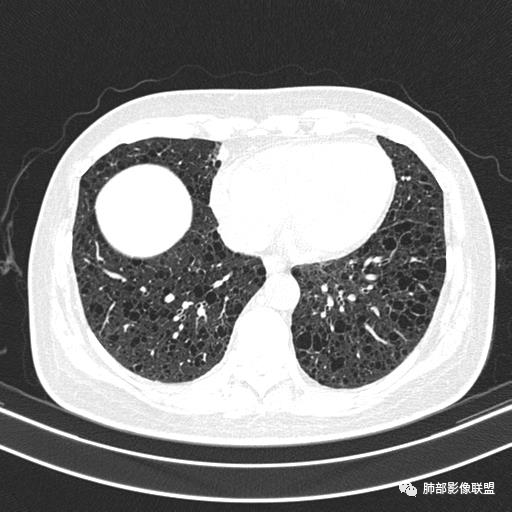

中年女性,不吸烟

双肺弥漫囊腔,累及肋膈角,囊腔形态相对规则单一。

符合LAM

CT平扫示双肺弥漫分布大小不等囊状薄壁透光区,无内、中、外带分布差异,间质稍示增厚。拟LAM

中年女性育龄期妇女,咳嗽气喘,无吸烟史,有苯吸入史。影像:双肺弥漫均匀小囊腔,无明显分布优势,囊腔形态欠规则,壁薄,部分囊腔边缘血管征,伴双肺弥漫磨玻璃影,无结节,考虑lam,鉴别苯中毒肺损伤,囊腔多有分布优势,小叶中心分布为主,形态规整等

女,46,活动性气喘1年。苯吸入史半年。胸部CT:两肺弥漫囊腔,上至肺尖,下至肋膈角,形态类似小囊腔。考虑:LAM,鉴别LIP,BHD,PLCH等。

双肺弥漫大小不一薄壁含气囊腔,囊间肺组织正常,正常肺背景,肺尖肺底受累;青年女性,气喘,支持LAM

双肺多发大小相近的囊状影,分布趋势趋于一致,中年女性,考虑LAM。部分囊内见血管及分隔影,小叶中心性肺气肿代排

CT表现:双肺弥漫大小不等的薄壁囊腔,囊壁<2mm,外形规则,血管影多位于囊腔周围,囊腔之间肺组织正常,随着疾病进展到晚期,囊腔变大、增多,不可胜数,囊腔可融合成较大的囊,与肺气肿相似,形成间质性肺纤维化。部分病例可出现结节影。